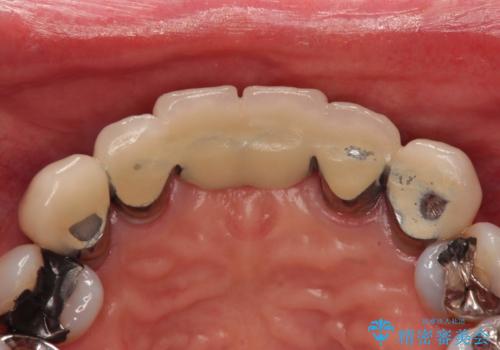

一見きれいにはいっているセラミックも、はずして中の状態をみるとひどいことが多い。これは、中の土台の状態や処理のクオリティは、短期的には問題を起こしづらく、患者さんには見えない部分だからです。

- 仮歯の製作、古い土台(メタルコア)の除去まで行い、根管治療は専門医に依頼